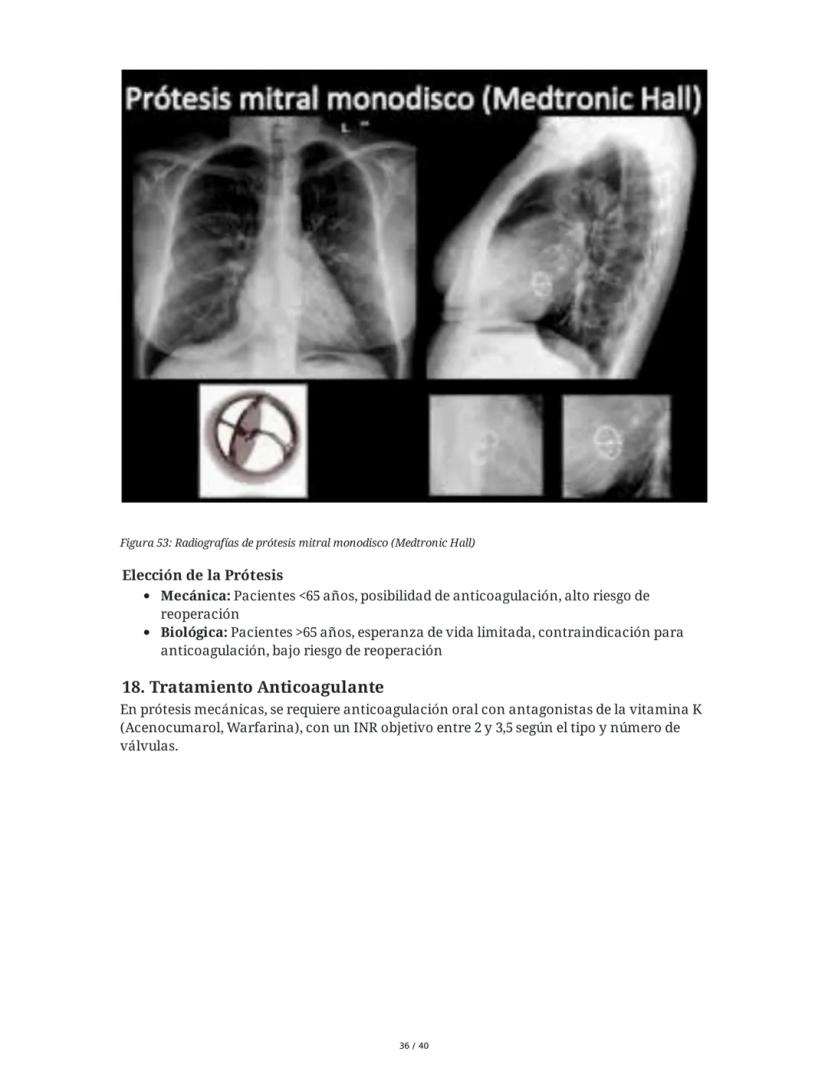

Sin embargo, cuando los síntomas son importantes y el daño miocárdico es reversible, se indica la reparación o recambio valvular. En patología valvular aguda, la cirugía suele ser urgente.